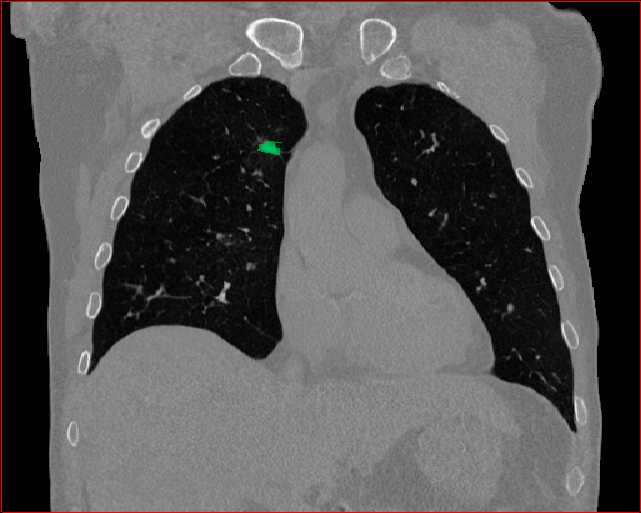

Figure 3 shows the generalizability of MAISI-v2 ControlNet for different body regions and voxel sizes. Figure 4 shows qualitative results for MAISI-v2 ControlNet on 5 types of tumors.

Lung Tumor

0.75×0.75×0.60.75\times 0.75\times 0.6

mm

512×512×512512\times 512\times 512

Figure 4: MAISI-v2 segmentation-guided results for five types of tumors. We show results for different voxel spacing and volume size to demonstrate the flexibility of MAISI-v2. Different Hounsfield Unit window is used to better show the contrast between tumor and normal tissues.